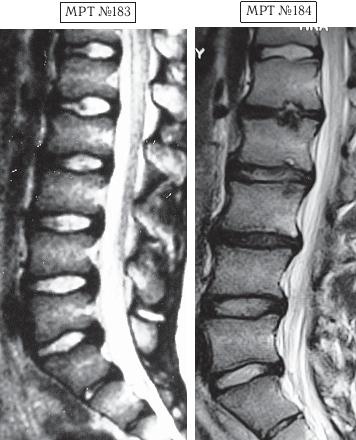

А вот второго парня вместе с его родителями я увидел только через полтора года после нашей первой встречи, когда они вновь пришли ко мне на консультацию в клинику. На этот раз состояние его позвоночника было удручающим. Оказывается, по инициативе родителей их семья посетила широко рекламируемую частную клинику, которая специализируется на кинезитерапии — лечение движением заболеваний позвоночника. Там с ними обстоятельно побеседовали по поводу того, как «активная кинезитерапия оказывает саногенетическое действие, устраняя патобиомеханический субстрат синдрома», что для людей, неискушённых в медицинских терминах, равносильно пафосной речи из советской комедии «Операция «Ы» и другие приключения Шурика»: «В то время, когда наши корабли бороздят просторы Вселенной…». А потом, чтобы пациент-клиент ничего не перепутал, выдали специальную брошюрку, где были подробно расписаны советы вместе с физическими упражнениями, направленными на укрепление мышц спины, которые по рекомендации врачей данной клиники необходимо было выполнять для «лечения» остеохондроза. К сожалению, на тот момент родители этого юноши не были осведомлены о негативном влиянии подобных упражнений, направленных на укрепление мышечного корсета, на позвоночник, поражённый дегенеративно-дистрофическим процессом. А когда случилась беда и пошли необратимые процессы, было уже поздно что-либо предпринимать. Вот уж правду в народе говорят: «Здоровье не купишь — его разум дарит».

На МРТ № 183 наблюдается состояние поясничного отдела позвоночника — начальная стадия развития остеохондроза практически во всех сегментах позвоночника.

На МРТ № 184 того же пациента — состояние поясничного отдела позвоночника после активного укрепления мышц спины физическими упражнениями (кинезитерапии): спондилёз, грыжи Шморля в сегментах ТXII—LI, LI—LII, LII—LIII, практически полное отсутствие межпозвонкового диска в сегменте L–Lu, значительное снижение высоты межпозвонковых дисков в сегментах LII—LIII, LIII—LIV, исправление физиологического лордоза, стеноз спинномозгового канала. Кроме того, помимо всего вышеперечисленного у пациента на уровне поражённых сегментов развился спондилоартроз.